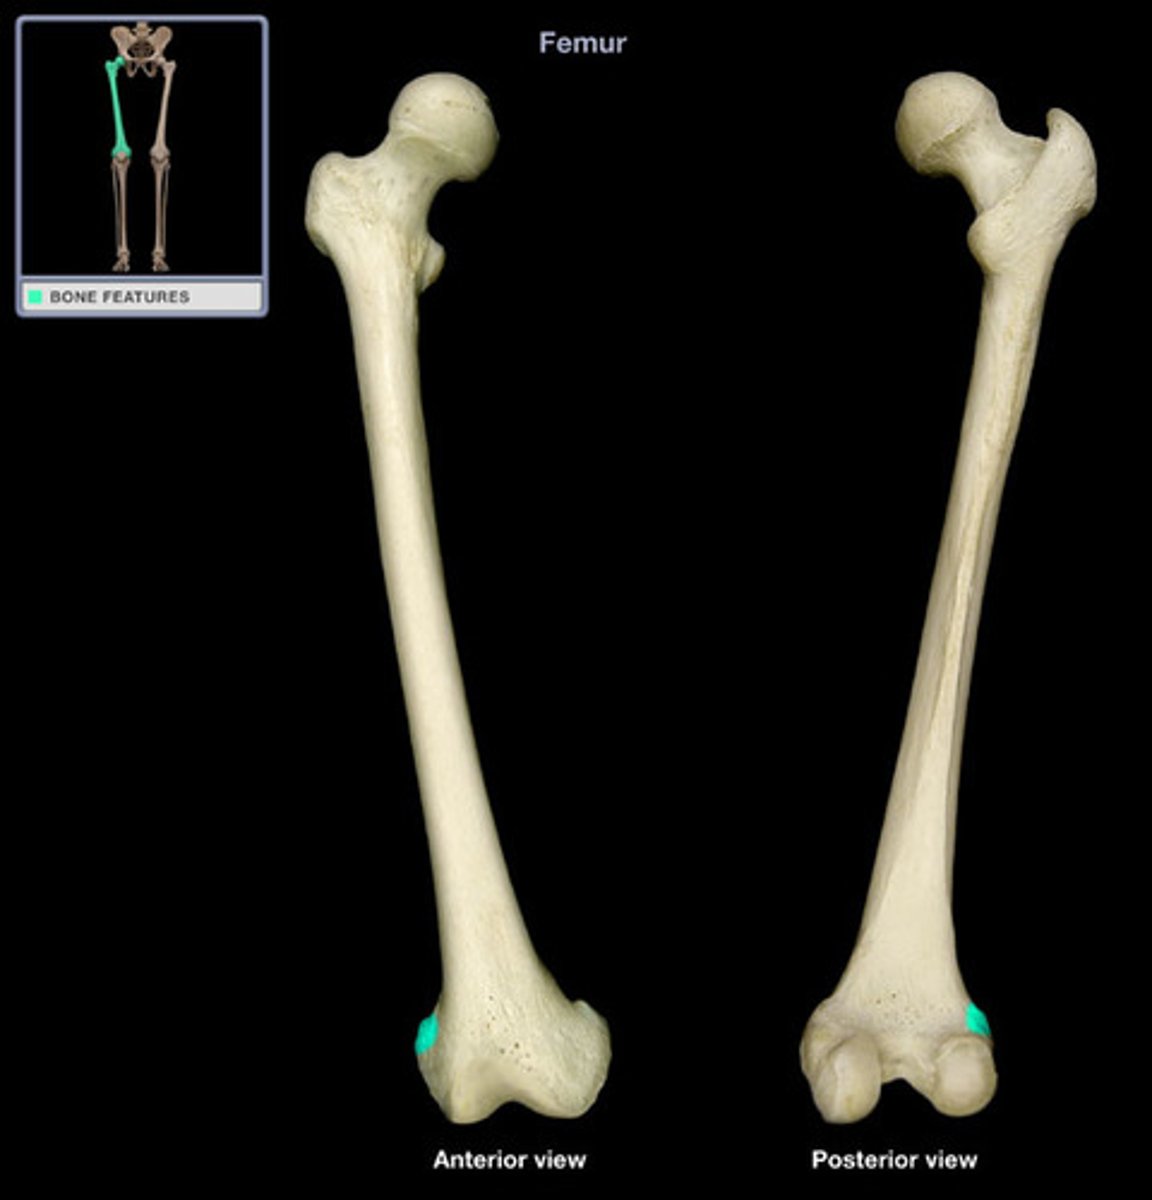

Femur

Medial Condyles of the Femur

Lateral Condyles of the Femur

Medial Epicondyles of the Femur

Lateral Epicondyles of the Femur